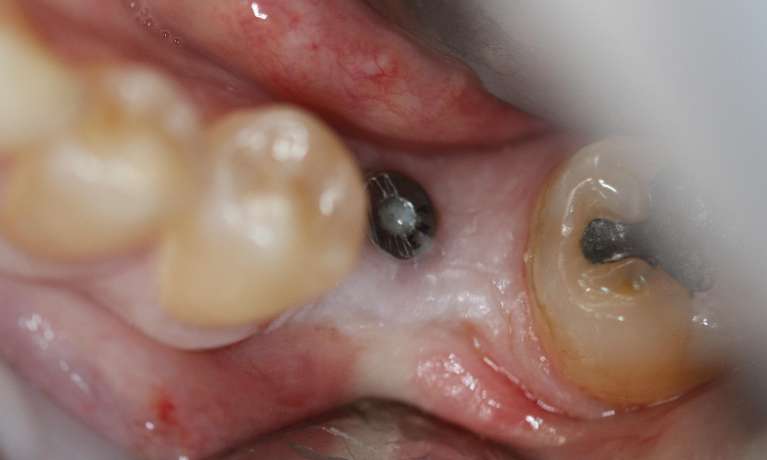

This patient had a missing back tooth replaced with a single, strategically placed dental implant. While not always visible, replacing a back tooth is crucial for maintaining proper chewing function and preventing surrounding teeth from shifting.

For this patient, dental implants were used to replace missing back teeth to help reestablish chewing efficiency and improve overall oral function.